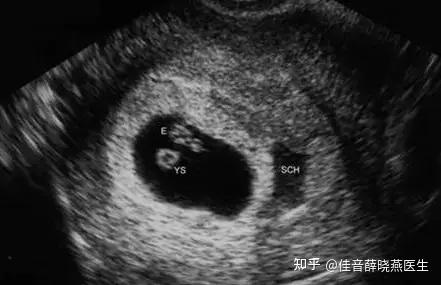

(图片来源网络,侵删)

- 早孕期(孕6-8周): 主要确认是否为宫内妊娠、胚胎是否存活、孕囊大小等,排除宫外孕等危险情况。